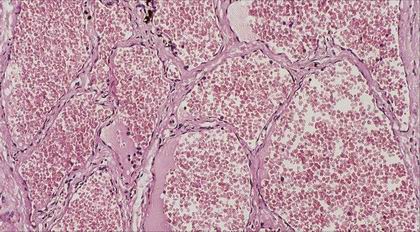

Nasopharyngeální angiofibrom